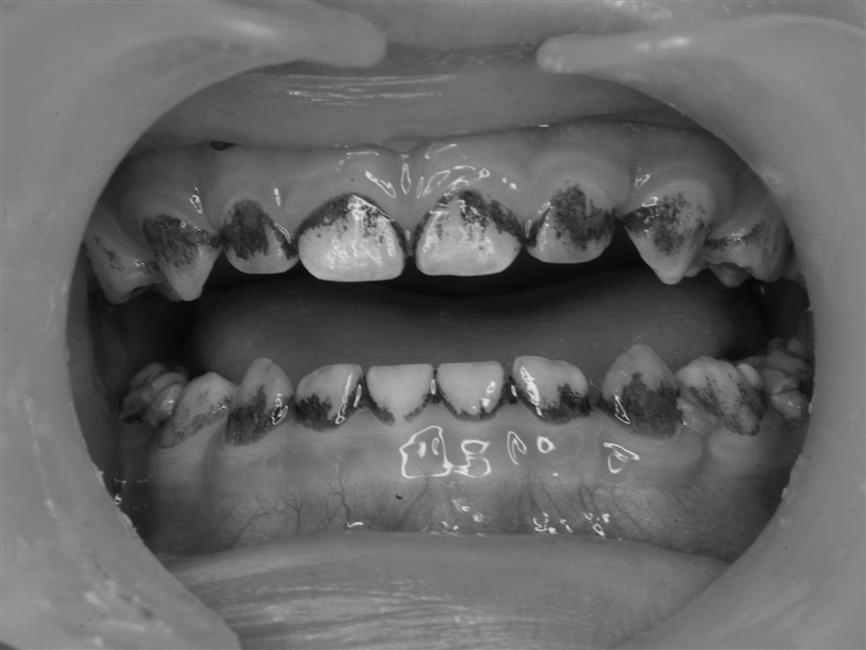

Ảnh minh họa về trường hợp mảng bám đen trên răng

Hiện tượng này gọi là black stain hay mảng bám đen trên răng, một tình trạng khá phổ biến ở trẻ em trên thế giới cũng như tại Việt Nam.

Đây là dạng nhiễm màu ngoại sinh, nghĩa là những chất tạo màu bám từ bên ngoài, chứ không phải do bản thân mô răng bị bệnh lý. Những mảng này thường xuất hiện thành chấm hoặc thành dải màu đen, chạy song song với viền nướu, đặc biệt rõ ở mặt trong của răng hàm dưới hoặc mặt ngoài của răng cửa trên.

Mảng bám đen bám rất chắc, khó làm sạch bằng cách chải răng thông thường và thường tái phát ngay cả sau khi bác sĩ nha khoa đã làm sạch. Tuy không gây đau đớn hay làm suy yếu răng, hiện tượng này ảnh hưởng đáng kể đến thẩm mỹ, khiến nhiều trẻ ngại cười và cha mẹ thì hoang mang.